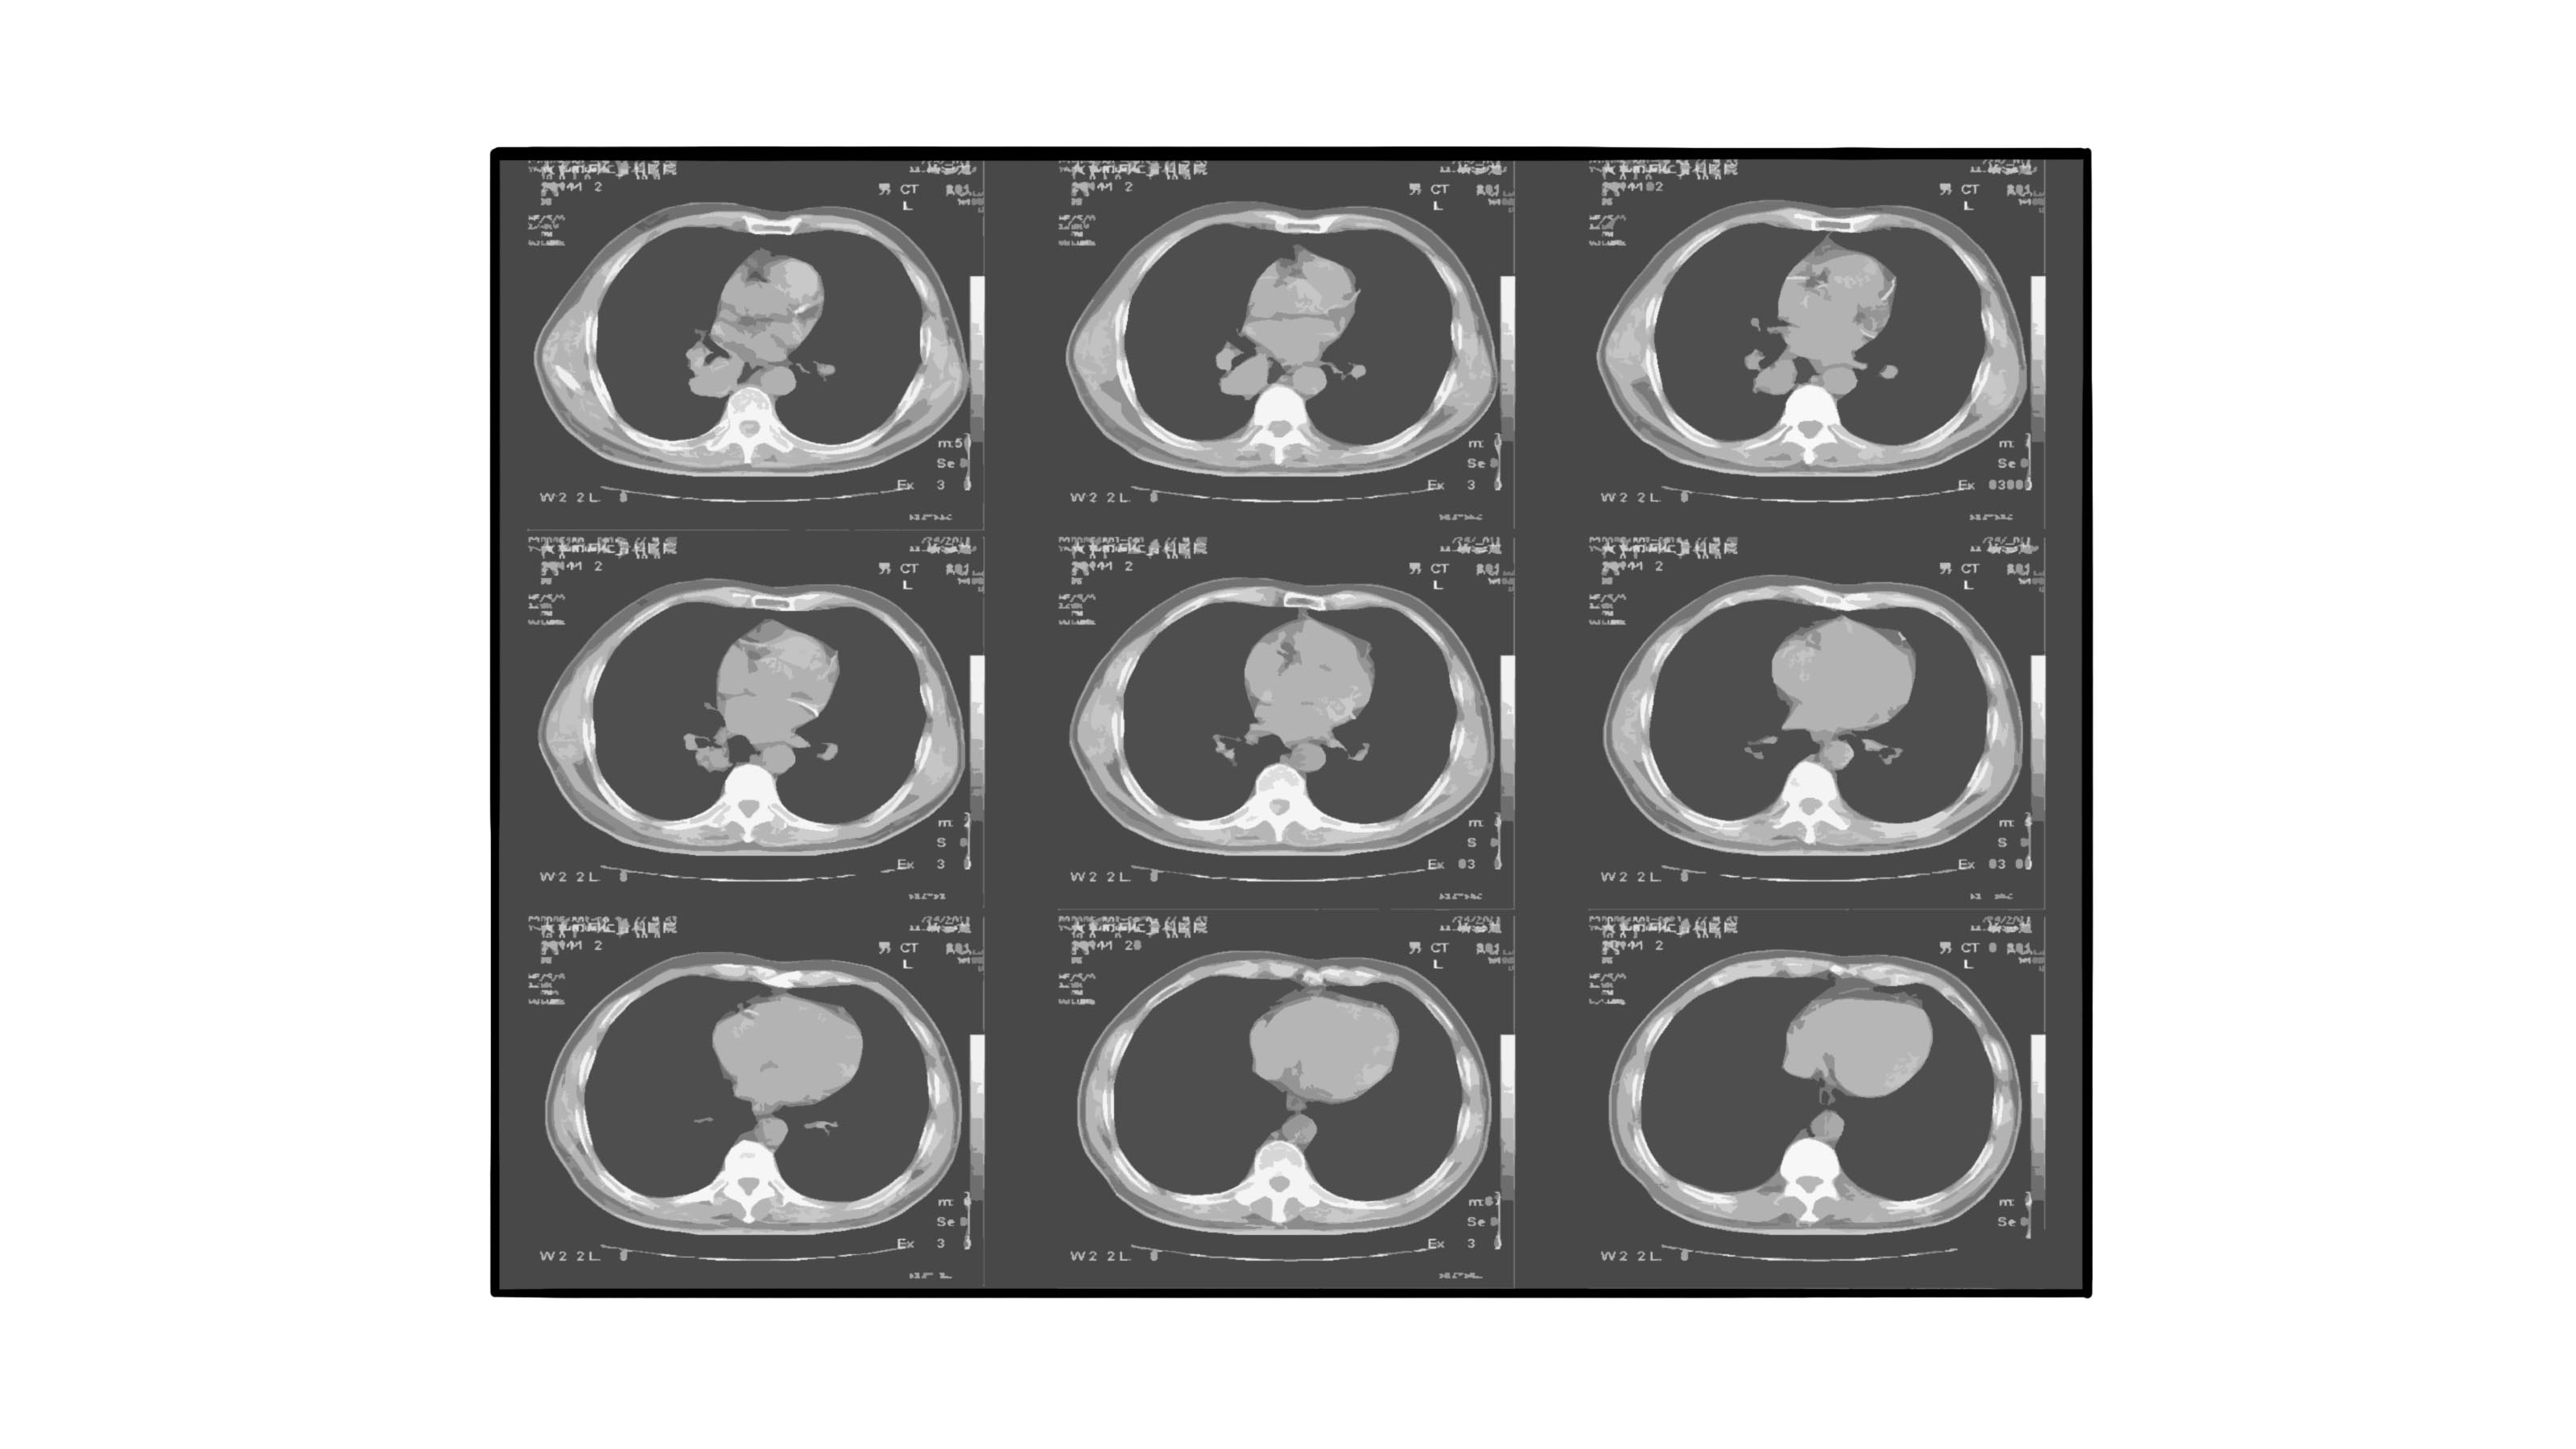

- 、肺癌:肺癌是起源于肺部支气管黏膜或腺体的恶性肿瘤。由于肿瘤组织迅速增大,会挤压周围组织,癌细胞转移扩散会浸润健康组织,CT检查时会发现有肺实质性肿块阴影、边缘不清晰、浸润明显等现象。